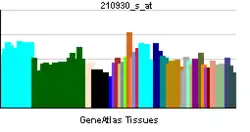

HER2 is a member of the human epidermal growth factor receptor (HER/EGFR/ERBB) family. But contrary to other members of the ERBB family, HER2 does not directly bind ligand. HER2 activation results from heterodimerization with another ERBB member or by homodimerization when HER2 concentration are high, for instance in cancer.[8] Amplification or over-expression of this oncogene has been shown to play an important role in the development and progression of certain aggressive types of breast cancer. In recent years the protein has become an important biomarker and target of therapy for approximately 30% of breast cancer patients.[9]

Amplification, also known as the over-expression of the ERBB2 gene, occurs in approximately 15-30% of breast cancers.[9][17] HER2-positive breast cancers are well established as being associated with increased disease recurrence and a poor prognosis compared with other identifiably genetically distinct breast cancers with other known, or lack thereof, genetic markers that are thought to be associated with other breast cancers; however, drug agents targeting HER2 in breast cancer have significantly and positively altered the otherwise poor prognosis of the historically problematic difficulties associated with HER2-positive breast cancer.[18] Over-expression is also known to occur in ovarian,[19] stomach, adenocarcinoma of the lung[20] and aggressive forms of uterine cancer, such as uterine serous endometrial carcinoma,[21][22] e.g. HER2 is over-expressed in approximately 7-34% of patients with gastric cancer[23][24] and in 30% of salivary duct carcinomas.[25]